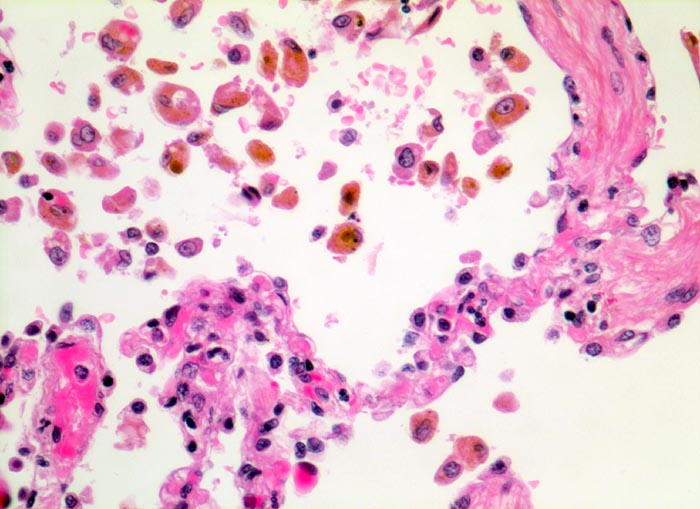

PathoPic – image database / PathoPic ID 5040 - chronische Lungenstauung: Herzfehlerzellen

chronische Lungenstauung: Herzfehlerzellen

Die Alveolarsepten sind deutlich fibrotisch verdickt. Gleichzeitig ist die Gefässausstattung vermindert. Die aus den Kapillaren in die Alveolarräume ausgetretenen Erythrozyten werden von Alveolarmakrophagen phagozytiert. Die Makrophagen enthalten teils intakte Erythrozyten, teils braunes Hämosiderinpigment aus bereits abgebauten Erythrozyten.

Patient mit Mitralinsuffizienz.